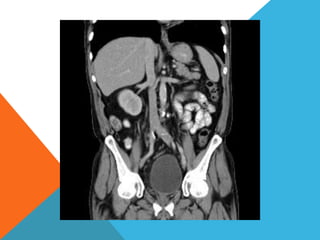

El paciente presentó síntomas de sangrado digestivo y pérdida de peso. Exámenes revelaron gastritis crónica asociada a H. pylori. Un tumor fue descubierto en una colonoscopia normal. La cirugía removió un tumor fibroide solitario, una rara neoplasia mesenquimal que usualmente crece lento y tiene bajo potencial de malignidad. El pronóstico después de la remoción quirúrgica es generalmente bueno.